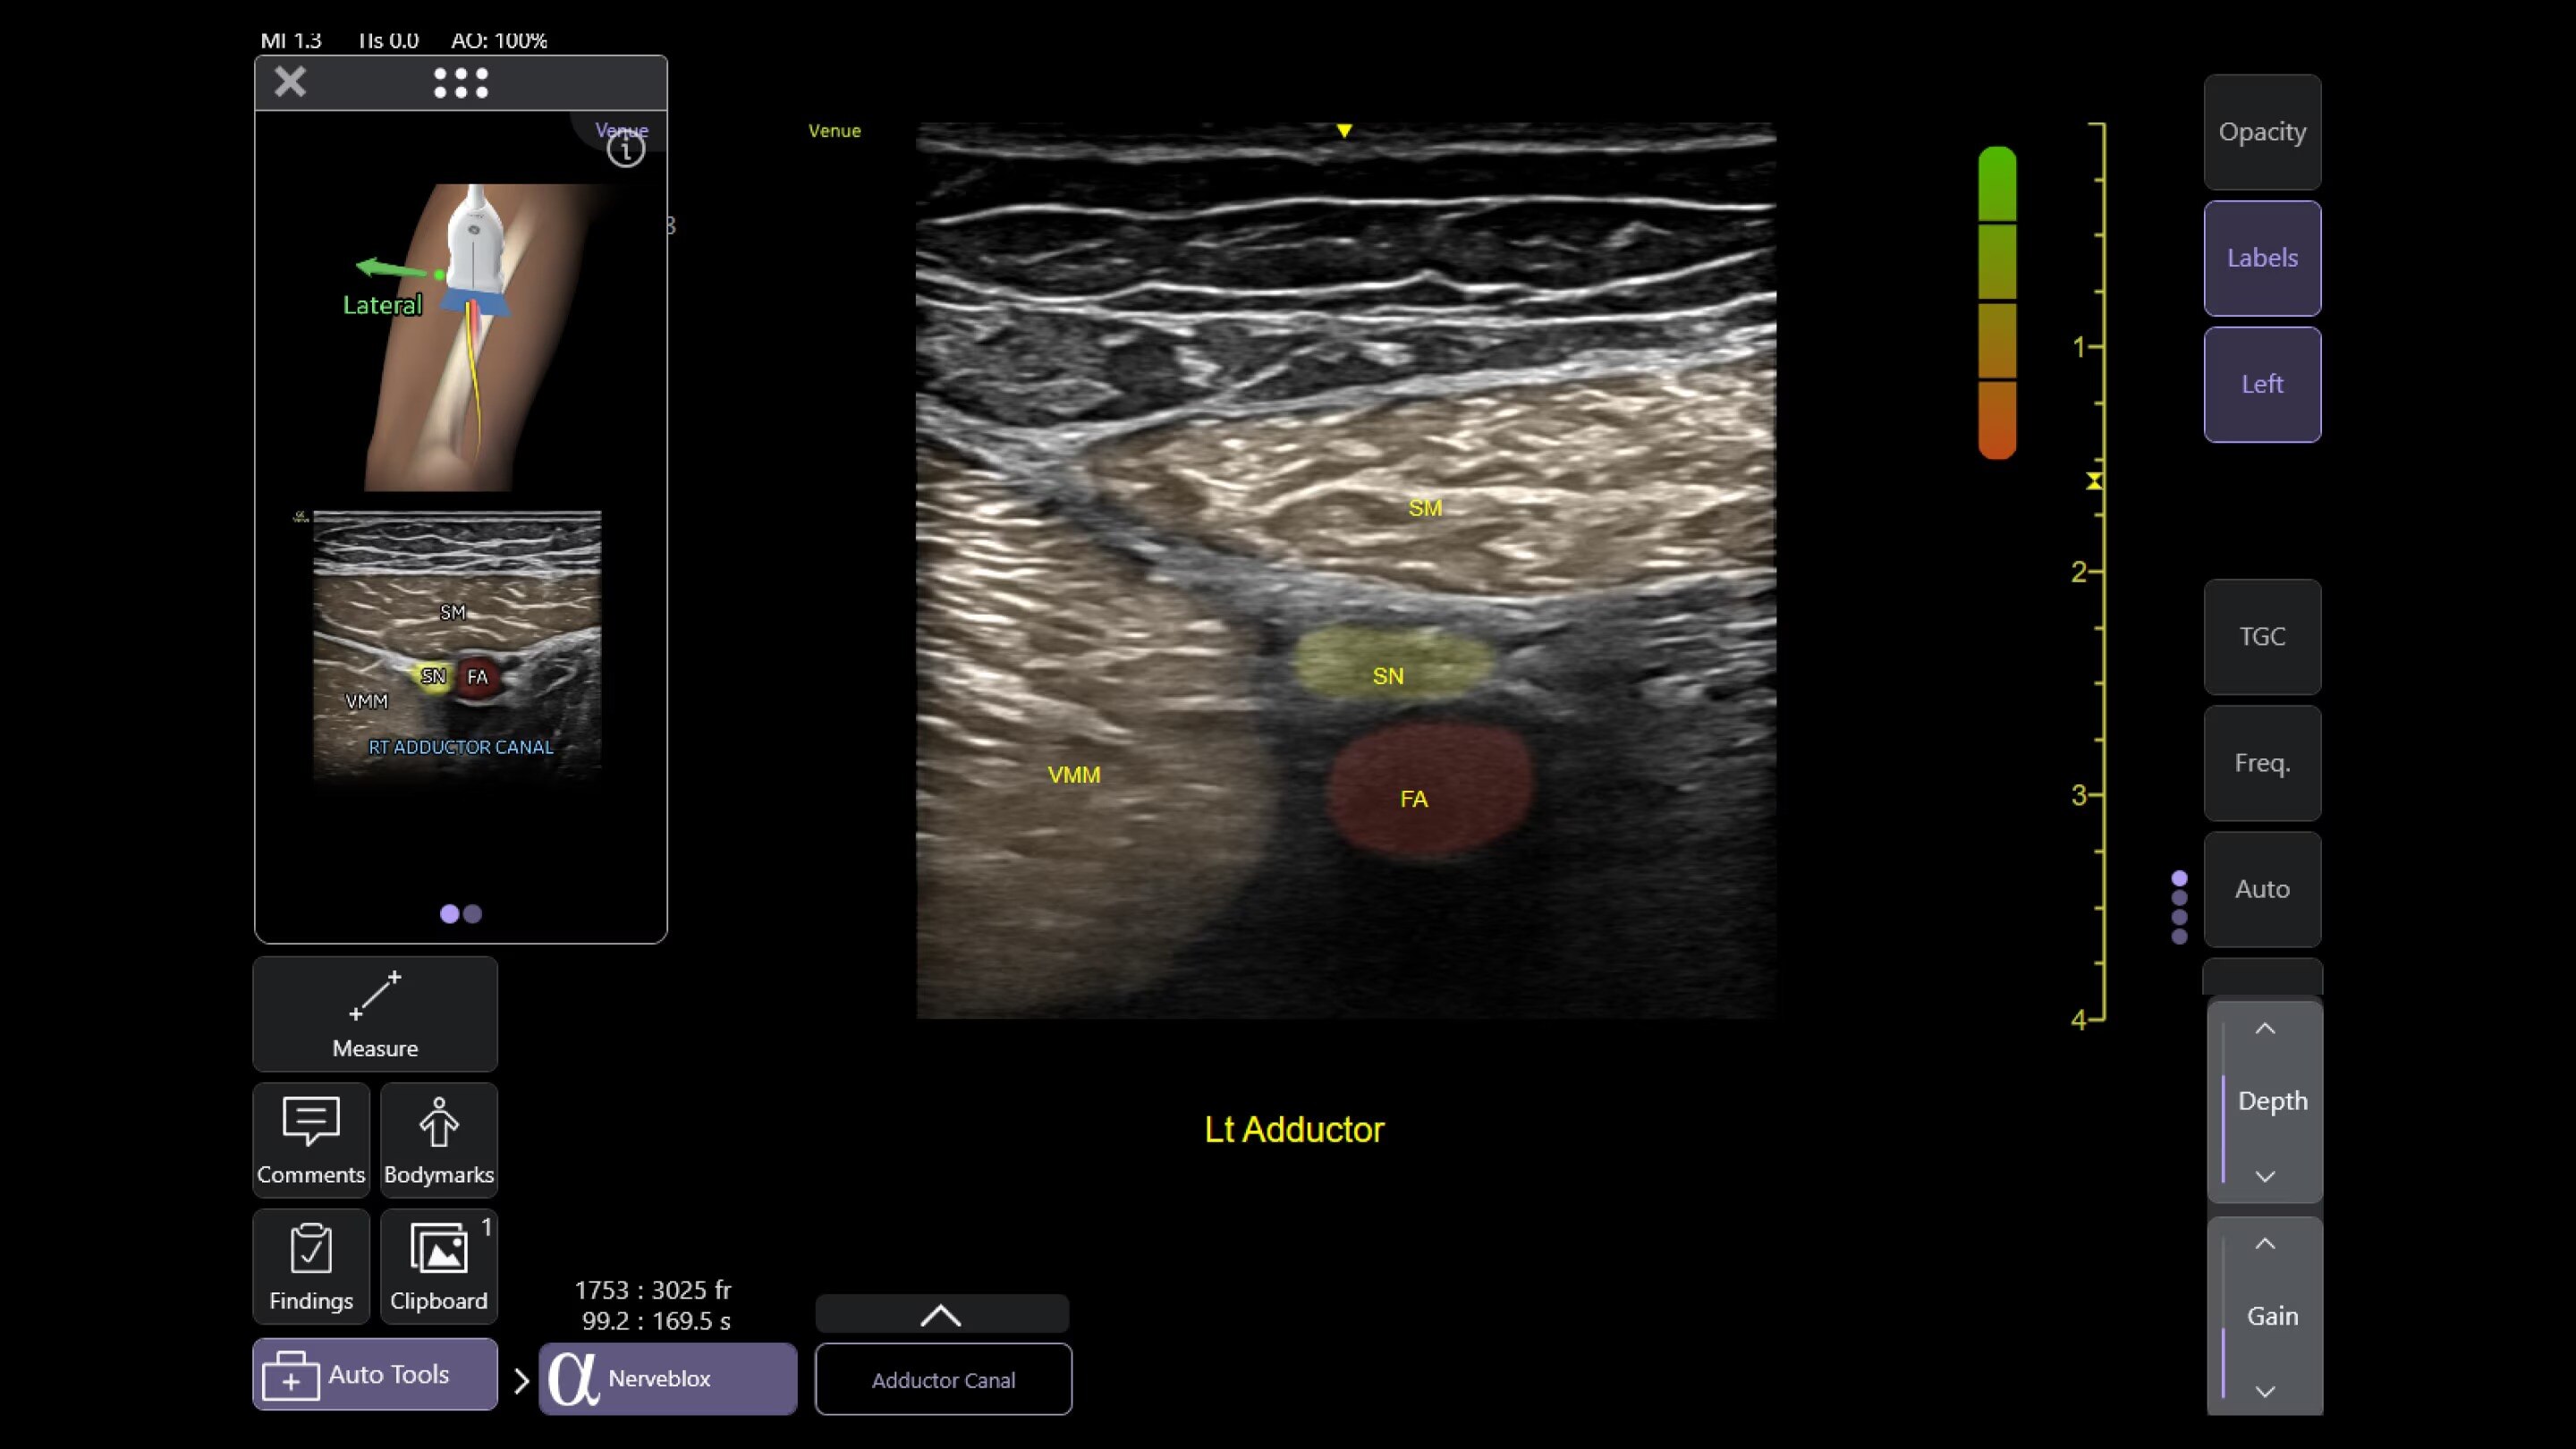

Nerveblox™

Perform ultrasound-guided peripheral nerve blocks with Nerveblox

Standard for Venue and Venue Go this AI-enabled tool automatically labels key anatomical landmarks in the ultrasound image, helping clinicians feel confident during the procedure and streamlining the workflow with the goal of reducing procedure time.